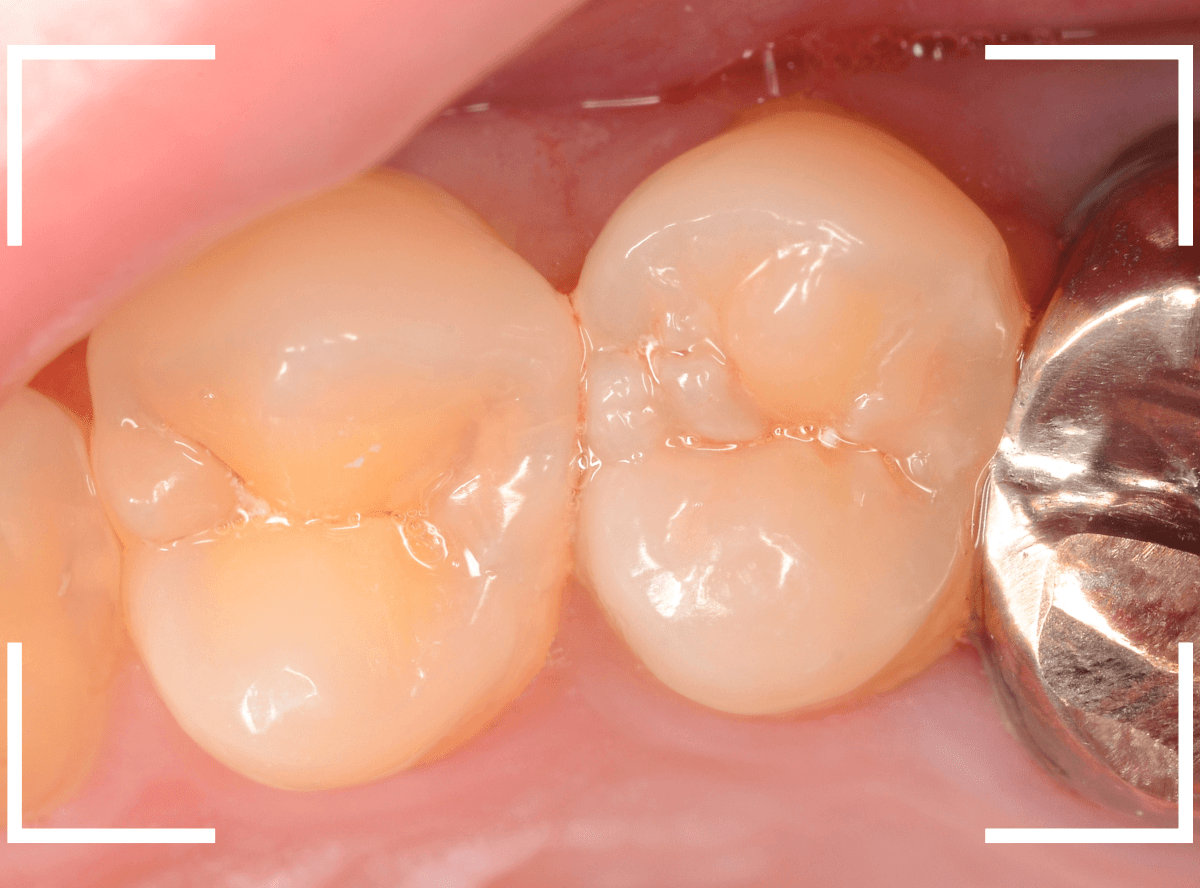

Case.22 痛みはないけど、歯のすきまから大きな虫歯

上の小臼歯の間が虫歯になっていた患者さんです。

症状はありませんし、見た目からも虫歯があるかはわかりませんでした。